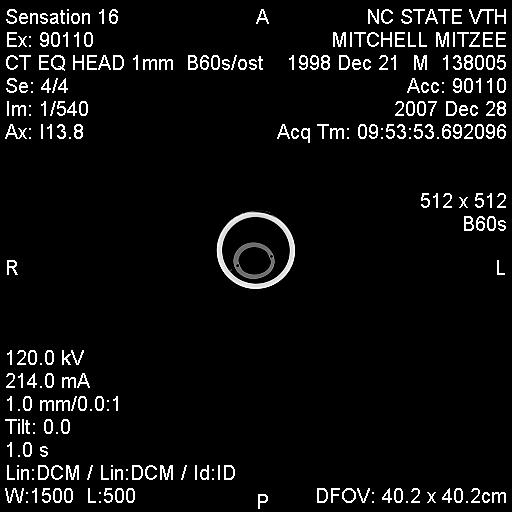

Posted on Sunday, Jun 24, 2007 - 3:39 pm: Greetings Everyone,I have finally received some of Mitzee's xrays, though it appears that I'm missing several... hmmm... Anyway, I thought I would give everyone an update. After two weeks of inpatient care (IV antibiotics, anti-inflamatory agents, a few different wound site I&Ds, several xrays and another fistulogram, etc...), she was discharged on 6/7/7. The final fistulogram showed NO evidence that the draining sinus tract communicated with the adjacent tooth root (4th premolar), but, rather, seemed to travel to the empty alveolar socket of her previous surgical site (the removed 3rd premolar). I had decided I did not want to attempt to manage her on my own, so I arranged to board her and Rorie at a facility owned by an equine vet, kind of like a lay up hospital situation... She's been getting daily assessment and care of her wound, the barn has a great fly control system and, so far, she usually goes out at night and stays in during the hot day. Plus, when she and Rorie are out, they're with other mare/foal pairs and that's a nice bonus for Rorie. Mitzee's eating well, her weight is good, and her activity is normal. And, though tissue healing is occurring, significant swelling of her left submandibular area persists and there are two remaining tracts that drain purulent material, though it is less than previously observed. I have decided to see how things go for awhile and "embrace" this conservative approach... clearly, the surgeon was not interested in pursuing more surgery at the time of her discharge, though when I corresponded with him recently (and showed the same pictures I am posting below) he suggested we get a CT scan. Of course, a CT scan appears to require general anesthesia and I would have to take her to a larger referral, probably academic, center. Based on where I am in VA, the closest facilities are NC State in Raleigh, NC, Marion duPont Scott in Leesburg, VA, or VA Tech in Blacksburg, VA... I do still worry that there's something "left behind" in the wound, perhaps a necrotic bone fragment???, that is continuing to feed this low level infection... At this point in time, she is almost 6 weeks postop from her initial surgery to remove premolar #3... Rorie was 8 weeks old last Tuesday... What does everyone think???? Thanks! Martha

Posted on Sunday, Jun 24, 2007 - 7:09 pm: I presume the folks who look at the original and complete set of radiographs, see no dead bone? Martha, considering everything, the swelling itself is not a bad sign and may take time to resolve. The radiograph is difficult to evaluate as it seems to lack much detail, possibly a problem with the generalized swelling. The parts we can make out look ok. Most important their is still purulent drainage, indicating the bodies attempt to rid itself of infection and/or necrotic material. As long as it is improving the conservative approach may work.DrO |

Posted on Sunday, Jun 24, 2007 - 8:57 pm: Thanks Dr. O and Everyone,Sorry, I know the film is somewhat poor... the surgeon's office girl sent me several films via an email attachment, so I wonder if when I downloaded them and reduced their sizes maybe I lost some resolution??? Hopefully, I will get a CD of all these films and can post better copies for your review... The surgeon reviewed all the films with me on the day of Mitzee's discharge and he felt pretty comfortable with everything being O.K. at that time, but, recently, when he saw the pictures I posted above, he suggested we get a CT scan... Dr. O, what's your take on that???... and, BTW, since you're in NC have you had "experiences" with NC State's vet school??? They're only down I-95/I-85 about 120 miles or so from Richmond and it would be a manageable trip to make, if needed... Regarding the issue I raised previously about hyperbaric oxygen therapy, I did talk to UT Knoxville and found out that their old chamber (a portable one) is not operational now in order to be replaced with an upgraded chamber (one that is permanently in place), hopefully sometime by the end of July... So, if there's ongoing evidence of infection, I still want to keep HBOT in mind... Thanks! Martha |

Posted on Monday, Jun 25, 2007 - 1:39 am: The picture quality IS poor, but it almost looks like there is some healing going on. |

Posted on Thursday, Dec 27, 2007 - 10:48 pm: Hey HA friends,Just wanted to say that Mitzee and I have arrived in the Tarheel state tonight! In a nutshell, for the past several months, Mitzee has continued to have intermittent serosanguinous vs. scant purulent drainage from her submandibular area and a significant ?fibrosed deformity of her jaw, though really no other indications of clinical problems... she's chewing well, weight is good, afebrile, etc... Sometime back in the summer, our equine surgeon had suggested that we undergo a CT scan (you guys may remember that even though Mitzee had significant purulence and edema following her initial surgery in May, the surgeon was very reluctant to "re-explore" the area due to the difficulty of that first surgery and the lack of evidence from her contrast fistulograms that the adjacent tooth root was involved in any infection)... So, though I had hoped to have her undergo this in the summer, NC State's Vet School was awaiting a "functional" table to use for equines in the scanner; and, though I was considering going to VA Tech instead, I had that little foot fracture in July which pretty much impaired my equine activities for several months. Given that she looked so good clinically, I decided to wait for NC State's table to be operational, but also given the continued appearance of the submandibular drainage, I still wanted to rule out any retained ?necrotic bone fragment or area of osteomyelitis in her mandible. So, tomorrow is the big day for the CT scan. The CT scan findings will direct any subsequent care, more surgery vs. medical therapy vs. nothing needed... I hope to get the CT films and post those sometime this weekend... wish us luck! Martha P.S. And, BTW, the other really wonderful thing is that I weaned baby Rory about a month ago (I changed the spelling of his name when I submitted his registration papers)... and in doing so, I moved Mitzee to another facility; well, I've spent alot of time with her over the past month and we have actually started to bond; she clearly has begun to trust humans and, in particular, me! Just the fact that I can groom her completely, touch every area of her face/head, even the submandibular area without too much protest, pick up her hooves (briefly) is all really wonderful! The new barn where I'm boarding her is a very busy hunter/jumper/eventing barn that gives a huge number of lessons, primarily to kids; Mitzee has really gotten desensitized to all the chaos that goes on and all the little girls at the barn just love her (she is the only Appaloosa there and her "rescue" history has made her interesting to everyone there)... I have really begun to marvel at the smarts this mare has and how willing she is to tolerate many different situations; I really believe that she will be under saddle in the next several months and that she will make a wonderful and safe mount! |

Posted on Saturday, Dec 29, 2007 - 9:43 am: Thanks for the update Martha and am surprised to hear you are having problems. The lack of problems on the last radiograph suggest this should have healed in most cases. There are two explanations:1) a foreign body, possibly a dead piece of bone 2) a resistant infection either bacterial or fungal Hopefully the CT scan will help better define the problem so it can be fixed but surgery with thorough debridement and good microbial work up are likely to be required whatever they find. Keep us appraised Martha. DrO |

Posted on Saturday, Dec 29, 2007 - 8:14 pm: Well, thanks for everyone's comments!Here's the scoop... the CT clearly showed infectious "involvement" of the adjacent tooth (left lower 4th premolar), though fortunately, the root and the pulp appeared to still be healthy; also, an area of the mandible inferior to the previously removed tooth (left lower 3rd premolar) had a "sequestrum", sort of under the now empty alveolar socket, which is well healed. So, immediately following the CT, after the surgeon reviewed it with the radiologist, Mitzee got moved to the OR (still under general anesthesia) and debridement of the affected areas began. Once the surgeon performed an oral exam, he was also able to demonstrate an orocutaneous fistula, corresponding to the exact area on her lateral jaw where she has had continued intermittent drainage for the past several months. The surgery and anesthesia were uneventful and she looked great when I left her last night (I'm on call today at work)... I will probably be able to pick her up as early as tomorrow, but that will depend on how much sleep I get tonight. Hopefully, I will be able to post some pictures of her xrays and CT scan for everyone to see... NC State has this great program, called Amicus, that "converts" the two dimensional information from the CT scan into three dimensional, COLOR, pictures and WOW, what information they reveal... just remarkable (I doubt I will be able to post any of those pictures due to the licensing issues with the software company)... Also, the veterinarians and staff of NC State have been AWESOME... I'll try to post pictures tomorrow... Martha |

Posted on Tuesday, Jan 1, 2008 - 11:08 pm: Hey Everyone,Sorry for the delay in posting the images... Mitzee was discharged on Sunday (POD 2) and I DrOve down to NC, picked her up, and travelled back to VA in the worst pouring down rain (not complaining, we still do have DrOught conditions a bit...) Anyway, I was on call the next day (New Years eve) and had a killer night, so I am still kinda brain dead today... I've managed to crash my laptop several times with the disc I was given at NC State... just wondering if it has anything to do with my new laptop OS, Vista, but now, finally, I've managed to load some of the study pictures onto my old laptop (hopefully the keyboard won't quit like it did this summer). The plain xray is not great... possibly me altering it in the download process??? Anyway, it is a lateral so you see both sides of the jaw and you have to focus on the near structures (the left side), not the far ones (the right side); basically, it shows distortion of the the left lower premolar #2, which has occurred following removal of #3 last May, and compensatory changes in the left upper arcade (see the big ramp/points above). The few CT views I've uploaded show extensive bony proliferation and periosteal reaction of the left hemimandible, an absent left lower 3rd premolar tooth, as well as some radioopaque densities below this area, presumed to be ?tooth fragments or cement debris following the previous surgery; there is one particular linear density located in the center of this area that was felt to represent a possible "sequestrum" and was removed... also, you can see a radiolucent tract that exits the lower portion of the left hemimandible below the empty alveolar area of the absent 3rd premolar. A lytic lesion is seen associated with the lateral aspect of left lower 4th premolar near the gingival margin and another draining tract travels between this front/rostral portion of the left lower 4th premolar tooth and the lateral aspect of the mandible; my discharge papers state that the CT findings "are consistent with peridontal abscessation and a draining tract", however the surgeon believes the root and pulp of the left lower 4th premolar tooth are still healthy, so we may have a ?50/50 chance of saving that tooth. I have also attached a few other pictures of Mitzee undergoing her CT scan under general anesthesia, her recovery from GA, and a view of the her face following the surgery where the diseased areas were debrided. Her discharge papers note the final diagnosis as "chronic osteomyelitis of the left mandible and peridontal disease adjacent to left mandibular premolar tooth #4". I'll keep everyone posted on her recovery. Thanks!!! Martha

Posted on Monday, Jan 7, 2008 - 4:56 pm: O.K., I am going to try and load the CT images again... please refer to my descriptions of them above. Also, the surgeon from NC State called me today and reported the results of the cultures taken during surgery; Mitzee has grown two types of anaerobic, gram negative rod bacteria, a Prevotella "species" and Fusobacterium nucleatum. He said that he had not had a Prevotella isolated from equines in the past, but that the Fusobacterium is a common oral bacteria in a number of species.... Now, the plan had been for Mitzee to receive two weeks of postop antibiotics, trimethoprim/sulfamethoxazole (Bactrim DS) and when I brought her home on POD#2, I was able to give her the PM dose by syringing paste directly into her mouth (she did protest a little); for the next 24 hours, I was on call and during my absence the barn staff failed miserably in getting any drug into her! I certainly didn't want any of the barn staff to sustain injuries, nor did I want Mitzee to be hurt (apparently, she got into her rearing mode...), so I spoke with the surgeon then and he said I could forego her oral antibiotics (afterall, the surgical debridement was the "definitive" therapy!). Today, he mentioned that metronidazole (Flagyl) was the typical antibiotic for anaerobes, but that horses tolerate it even less than the Bactrim she had been on... so, since he felt good about the debridement, we are not treating her with antibiotics. The plan is to (as long as she looks good "clinically") take her back to Raleigh in about 4 weeks so he can examine her oropharynx and HOPEFULLY see that her orocutaneous fistula is HEALED and that the left lower premolar #4 is still O.K.!!! I'll keep everyone posted!Martha P.S. Keep in mind, when looking at the scans below, you are looking at a "cross-section" or axial image of the head, UPSIDE down... remember that she was laying on her backside to undergo the scan... also, the right side of the image is Mitzee's left side... notice the dramatic difference between the two sides, i.e., each hemimandible...

| Moderator: DrO |

Posted on Tuesday, Jan 8, 2008 - 8:07 am: They really caught the fistula and infected mandible well. Good luck with the surgery outcome Martha.DrO |